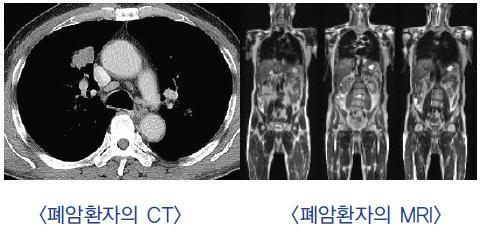

폐암은 원발성 폐암을 말하며 원발성 폐암은 폐에서 기원하는 악성 종양을 말한다. 폐로 전이된 암은 폐로 전이된 것으로 분류되며, 폐암이라기 보다는 기원 장기로 전이된 것으로 분류된다. 폐암은 조직학적 유형에 따라 크게 소세포폐암과 비소세포폐암으로 분류된다.

이 분류의 이유는 소세포 폐암이 치료 및 예후 측면에서 다른 유형의 폐암과 확연히 다른 특징을 가지고 있기 때문입니다.